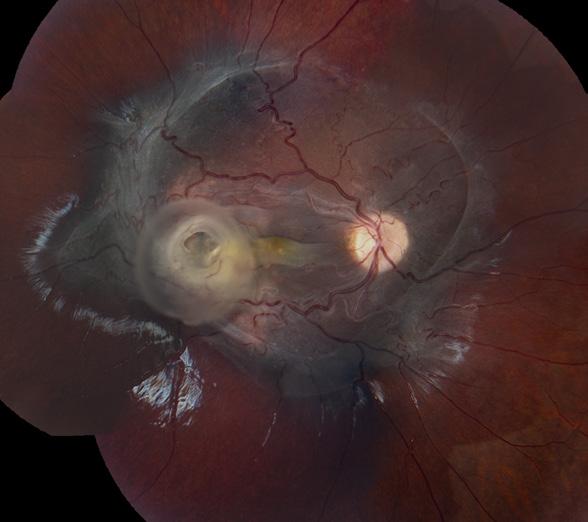

Photo/Electron Micrography

Tapioca Melanoma SEM

Ralph Eagle Jr., MD

Wills Eye Hospital, Philadelphia, Pennsylvania

Photo/Electron Micrography

Tapioca Melanoma SEM

Ralph Eagle Jr., MD

Wills Eye Hospital

Philadelphia, Pennsylvania